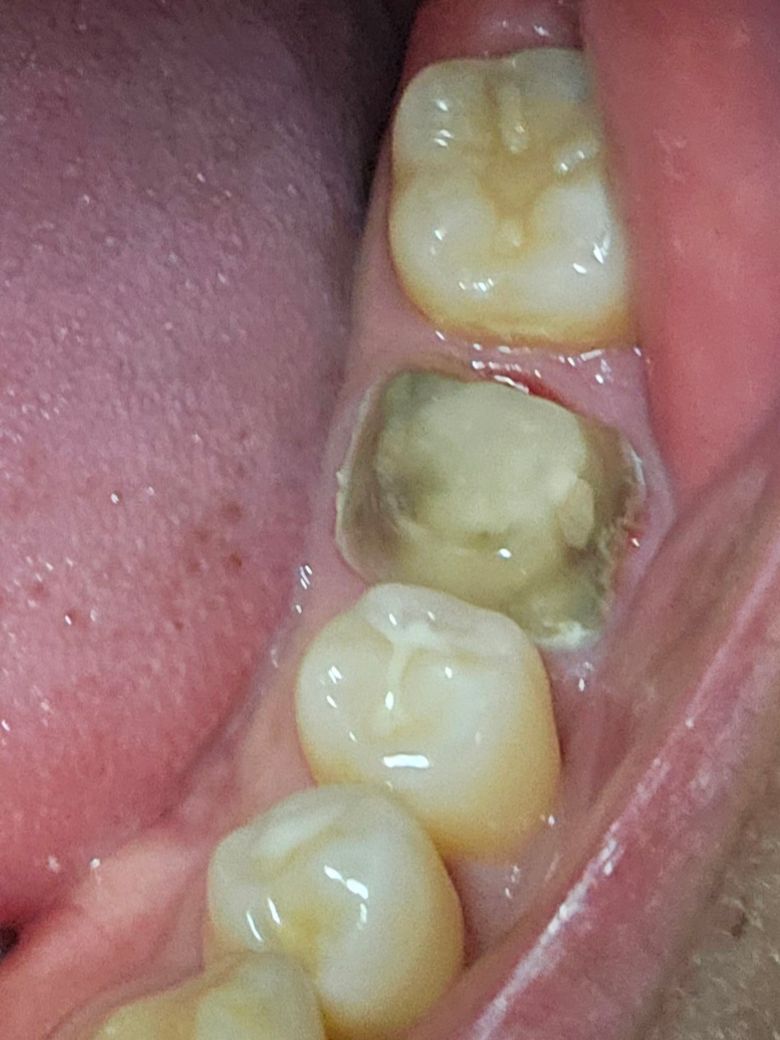

크라운이 빠졌는데 이빨이 까맣게 변해있어요

신경치료하고 크라운 씌운지 1년도 안됐는데 크라운이 밥 먹다가 빠졌어요. 크라운에서 편도결석 냄새도 나고 이빨은 사진처럼 검게 변했어요 코어 부분은 그나마 괜찮은거 같은데 원래 제 이빨이었던 부분들은 검게 변했는데 뭐가 잘못된걸까요?

사진으로만 봤을 경우에 검은색은 충치라기보다도 치아색이 착색이 된 것일 가능성이 높습니다. 검은 부분을 모두 제거하려고 하다 보면 치아가 거의 남지 않게 되어 오히려 치아가 약해질 수 있기 때문에 충치가 아닌 착색된 부위라 함을 제거하지 않는 경우도 있습니다. 자세한 확인을 위해서 직화에서 진료를 받아보는 것을 권유드립니다

추가적인 충치가 발생하였을 가능성이 있기에 이 경우 추가적인 치료후에 크라운 치료가 필요로 됩니다. 만약 충치의 정도가 깊은 경우에는 재신경 치료가 필요로 됩니다.

크라운 내부에 내부우식이 생긴 것이 의심됩니다.

어두운 부분은 좀 제거하고 코어를 다시 한 후에

크라운을 재제작하는게 좋아보입니다.